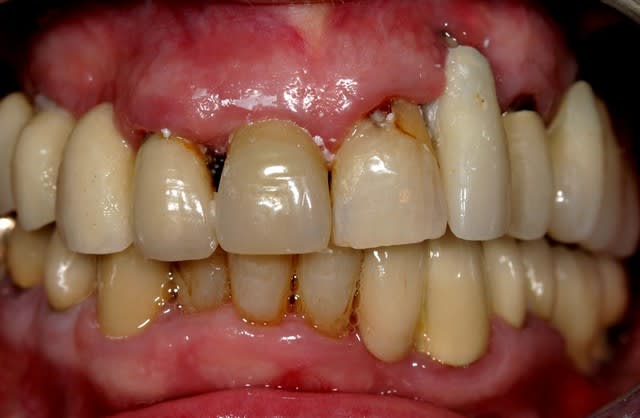

Le conjonctif sur la 22...je vois pas comment ça pourrait prendre je vois presques des spires de l'implant...

intéressants, les implants zygomatiques qui s'arrêtent au quart du chemin. d'un point de vue biomécanique, ce traitement implantaire, c'est n'importe quoi. les édentements terminaux à droite et à gauche doivent être soutenus par 3 implants minimum, de préférence ostéo-intégrés, et de préférence pas dans la cavité sinusienne (il se peut que les implants soient placés dans une paroi sinusienne en évitant la cavité, mais je doute). la ligne de gencive sur l'implant en 22 est irrécupérable, car il n'y a rien pour soutenir une greffe. ce que je ferai:

je viens juste de découvrir ce cas. Les voyants se mettent au rouge! J'ai pas besoin de microscope pour voir de suite que ce cas pue le paropathogène à fond!